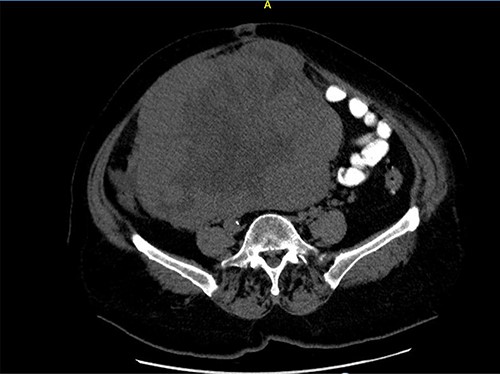

A 68-year-old female patient presented with a palpable abdominal mass in the lower parties of the abdomen. Three months earlier, she noticed painless abdominal distension and frequent urination. She underwent hysterectomy without oophorectomy for treatment of uterine myoma 12 years ago. The results of the transabdominal ultrasound and cross-sectional scan showed a 22 × 21-cm abdominopelvical mass, more right-sided, with both solid and cystic components, and incipient hepatomegaly with single hypodense lesion of liver, 8 mm in diameter. Blood test showed elevated serum cancer antigen 125 (CA 125) 185.9 U/ml, human epididymis secretory protein 4 (HE4) 228.3 pmol/l levels, and the risk of ovarian malignancy algorithm index (Roma index) was high with 79.9%. After a laparotomy, large tumorous mass 22 × 21 cm in diameter was found, which was grayish brown to yellowish color with nodular surface and cystic components, occupying the entire abdominopelvic cavity. (Figs 1 and 2) The tumor was well encapsulated and solid, fixated to the omentum and mesentery with large, nutritional, blood vessels and to surrounding tissue (Figs 3–5). Complete surgical resection of tumor, including bilateral adnexectomy, was performed. The post-operative period was uneventful. After 6 months of follow-up, magnetic resonance imaging of the abdomen and pelvis was performed, and there were no signs of tumor recurrence and serum levels of tumor markers were in reference ranges.

Axial computed tomography (CT) scan shows solid mass in abdominopelvic cavity.

Close picture of axial CT scan of tumor, showing more right-sided localization.